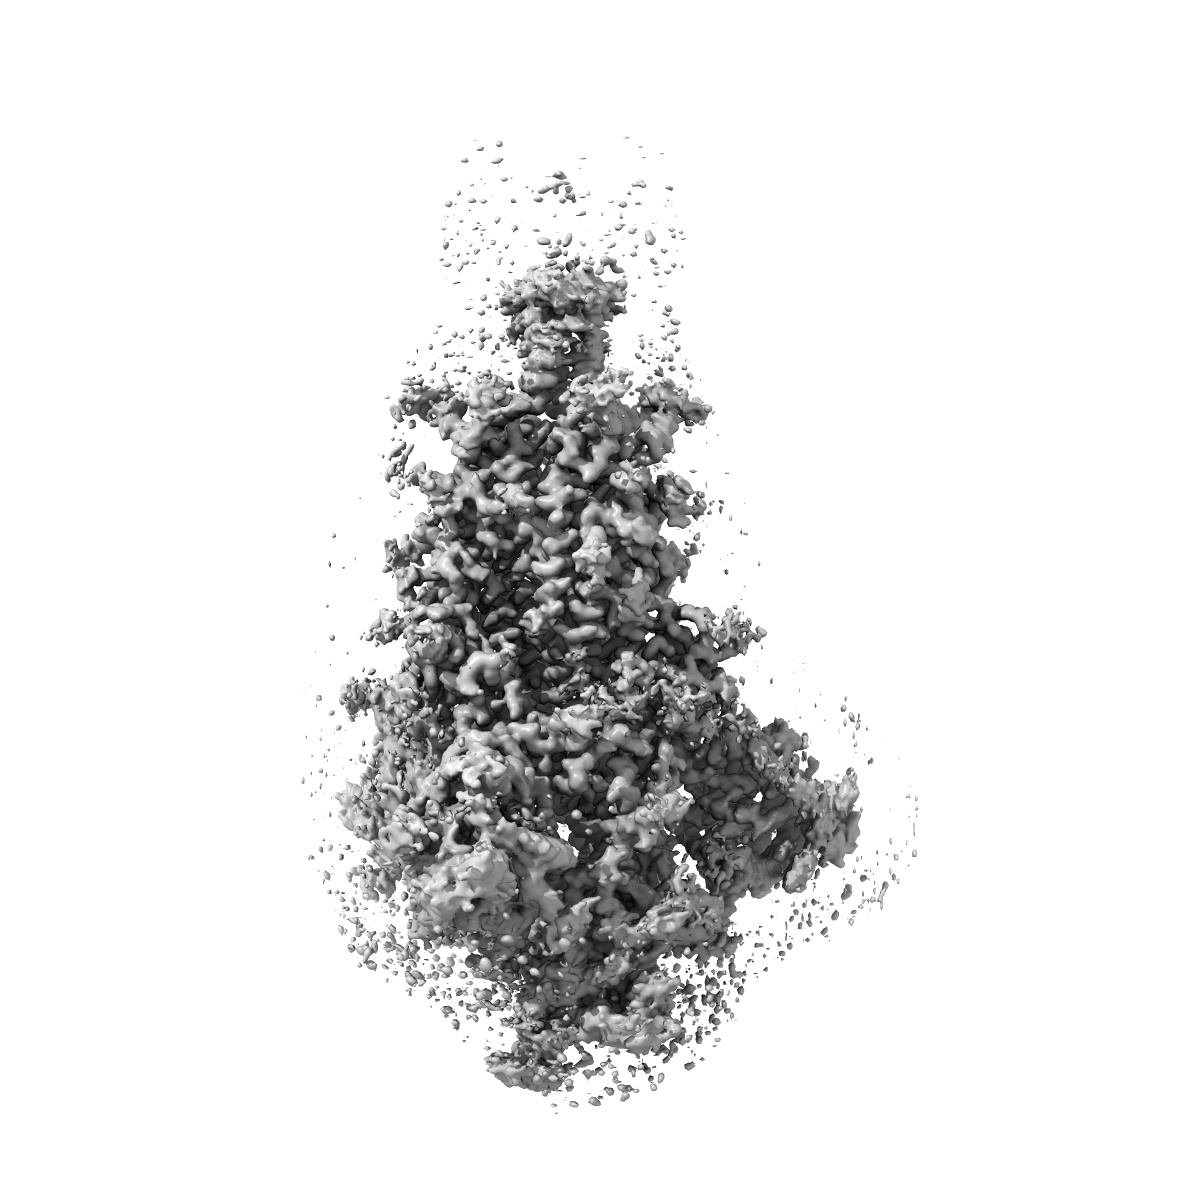

Structural basis for enhanced infectivity and immune evasion of SARS-CoV-2 variants

Single-particle3.21 Å

Sample: one RBD-up-2 of pre-fusion SARS-CoV-2 B.1.1.7 spike variant glycoprotein

Structural basis for enhanced infectivity and immune evasion of SARS-CoV-2 variants.